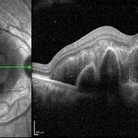

Polypoidal Choroidal Vasculopathy

May 25 2024 by T. P . VIGNESH, MBBS,MS

SD- OCT of the left eye of a 65 year old man revealing multilobulated large PED.

Photographer: Sivanath

Imaging device: Heidelberg Spectralis

Condition/keywords: polypoidal choroidal vasculopathy (PCV)